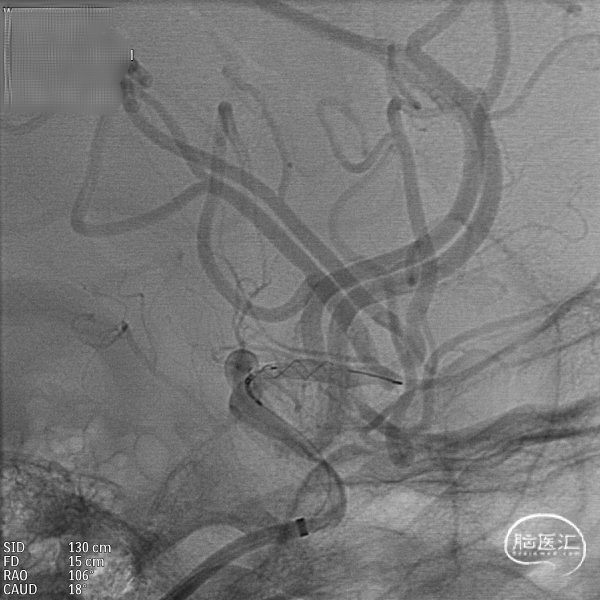

支架到位,远端打开(正侧位):4.75-20mm支架在大脑中动脉M1段打开,回撤至C6段远端锚定。支架释放过程中,轻柔推送支架系统,可见支架导管沿血管壁大弯侧走行,支架打开良好。

支架中段打开:

输送导丝及微导管回撤:释放至支架末端,减张系统,回撤支架导管,释放支架。沿支架推送杆,调节系统张力,将支架导管通过支架到达C7段。

支架内使用成襻微导丝进行按摩,使支架充分贴壁。

术后造影:支架覆盖两枚动脉瘤瘤颈,贴壁良好,瘤体内可见造影剂滞留。

术后支架显影: